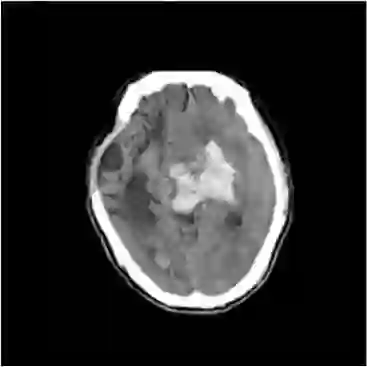

The midline related pathological image features are crucial for evaluating the severity of brain compression caused by stroke or traumatic brain injury (TBI). The automated midline delineation not only improves the assessment and clinical decision making for patients with stroke symptoms or head trauma but also reduces the time of diagnosis. Nevertheless, most of the previous methods model the midline by localizing the anatomical points, which are hard to detect or even missing in severe cases. In this paper, we formulate the brain midline delineation as a segmentation task and propose a three-stage framework. The proposed framework firstly aligns an input CT image into the standard space. Then, the aligned image is processed by a midline detection network (MD-Net) integrated with the CoordConv Layer and Cascade AtrousCconv Module to obtain the probability map. Finally, we formulate the optimal midline selection as a pathfinding problem to solve the problem of the discontinuity of midline delineation. Experimental results show that our proposed framework can achieve superior performance on one in-house dataset and one public dataset.